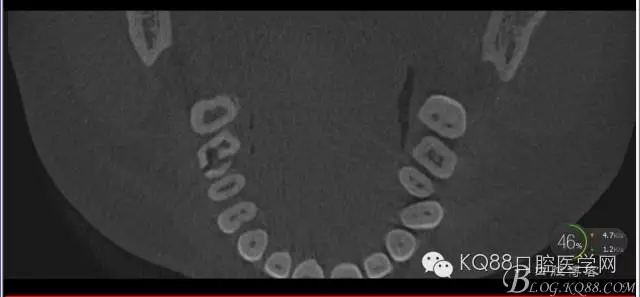

下面是拔牙后三個(gè)月的CBCT。垂直骨高度約6.7mm。

另外一個(gè)切面。垂直骨高度不夠,準(zhǔn)備 :做內(nèi)提升,植骨,植入植體。